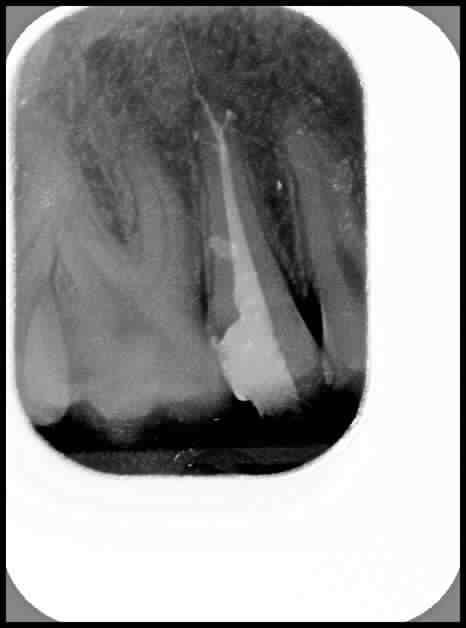

en regardant la radio, pouvez vous me dire si ce que je vois au delà de l'apex de cette 15 est bien le morceau de Ni-Ti que j'ai fracturé (instrument S1)?

Je suis persuadé qu'il s'est fracturé près de la constriction apicale et pas au delà; aurais-je pu l'expulser lors de l'obturation au compactor????

Cela ressemble plus à une fusée du sealer.

Merci, me voilà à demi rassuré... mais je trouve que c'est bien rectiligne pour du sealer quand même!

Pour le petit trait radioopaque à l'apex, la résolution de l'image postée ne permet vraiment pas de conclure.

ça ne ressemble pas trop à un bout de protaper.

ça ressemble plus à une fusée du ciment canalaire qui aurait vraisemblablement suivi un dépassement éventuel à la lime 10 ou 15.

Bien sûr que si, je compte et fais vérifier à mon assistante mes instruments... mais en l'occurence c'était un S1 neuf! Je parle bien du trait rectiligne au delà de l'apex. Je suis persuadé d'avoir cassé un bout de l'instrument car je l'ai mesuré et bizarrement, il ne faisait que 23 mm...

Le trait est très probablement une fusée de ciment, par contre en regardant bien tout près de l'apex dans la gutta on semble voir un petit morceau plus dense non ?

C'est très possible en effet que ce soit la zone hyperdense près de l'apex. Si vous êtes tous d'accord sur une fusée de ciment... ça me rassure.